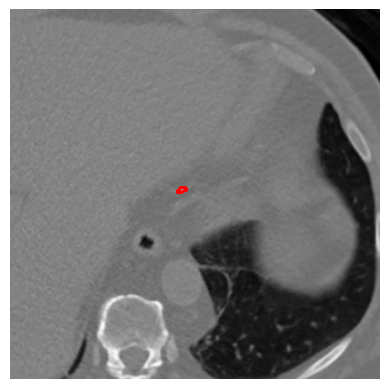

Refer to caption

(a) Annotated CT slice with annotation

(b) CT slice without annotation

(c)

(d)

(e)

(f)

(g)

(h)

Figure 2: Representation of guided local data augmentation. Figure a𝑎aitalic_a represents labeled CT slice, while b𝑏bitalic_b represents the same image without annotation. The figures from c𝑐citalic_c to hhitalic_h shows the guided local data augmentations utilized in DINO training.

Label-guided augmentation is effective for the data with only labels or prompt points. During the training phase, CT slices with annotations or labels are randomly augmented regardless of whether they have labels. In addition to this random augmentation, it is applied an augmentation which centers the center of annotated areas chosen randomly from labels. This point specific augmentation helps the model to emphasize on that labeled areas more than other randomly chosen and cropped areas. The point specific data augmentation or label-guided data augmentation has been applied for local data augmentations rather than global data augmentation, as the areas we want to highlight in features generated by DINO contain more localized information. The Fig. 2 represents locally guided data augmentation on a CT slice which includes a calcification. In our experiments, random local data augmentation was set to 8888, while guided local data augmentation was set to 6666, in order to preserve the randomness of the local data augmentation process. To illustrate the contributions of guided data augmentation, Fig. 3 presents a visualization of the outputs from the self-attention heads of DINO models trained using both label-guided and standard methods.